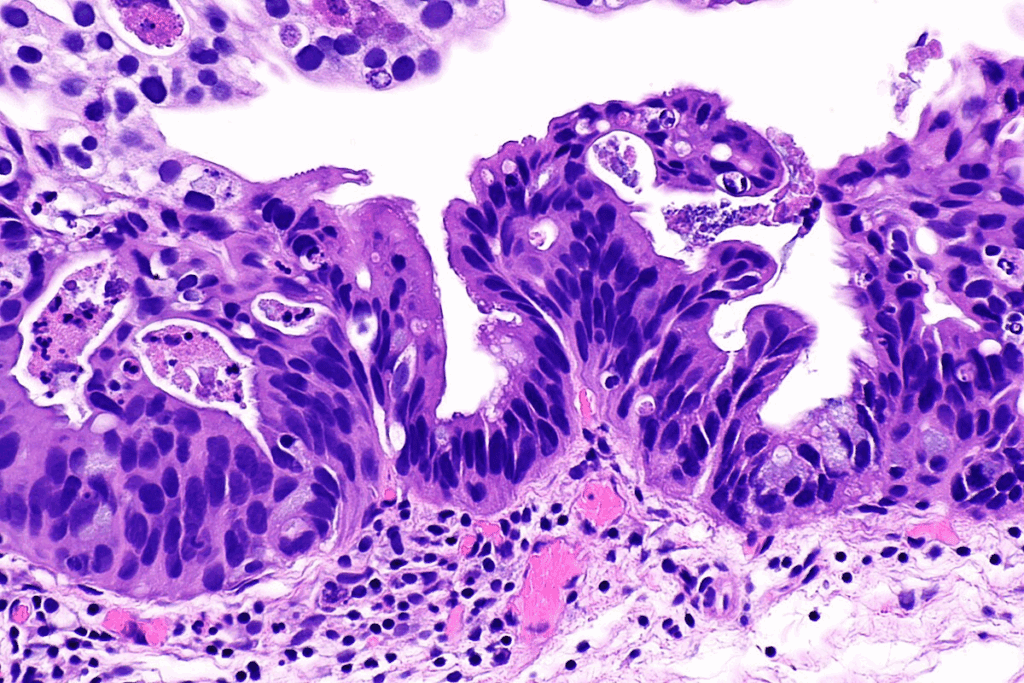

Microscopic Identification of In Situ Cells

Looking at cells under a microscope is key to spotting CA in situ. Doctors search for signs like unusual nuclei and cell shapes. Finding these signs helps tell CA in situ apart from normal cells and cancer. This is important for choosing the right treatment and understanding carcinoma situ meaning.